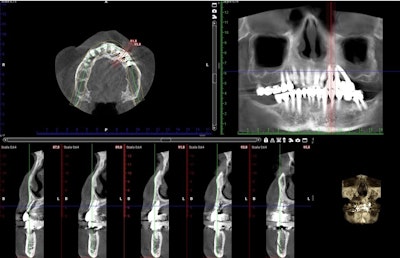

Digital implant project: three different views of the same procedures.

X-ray and CBCT post-op.